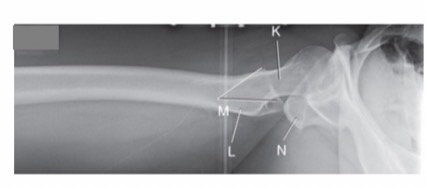

What projection/position is this?

Axiolateral Inferosuperior

What is another name for this method?

Danelius-Miller Method

Name Area K

K. Femoral Neck

Name Area L and M

L. Lesser Trochanter

M. Greater Trochanter

Name Area N

Ischial Tuberosity